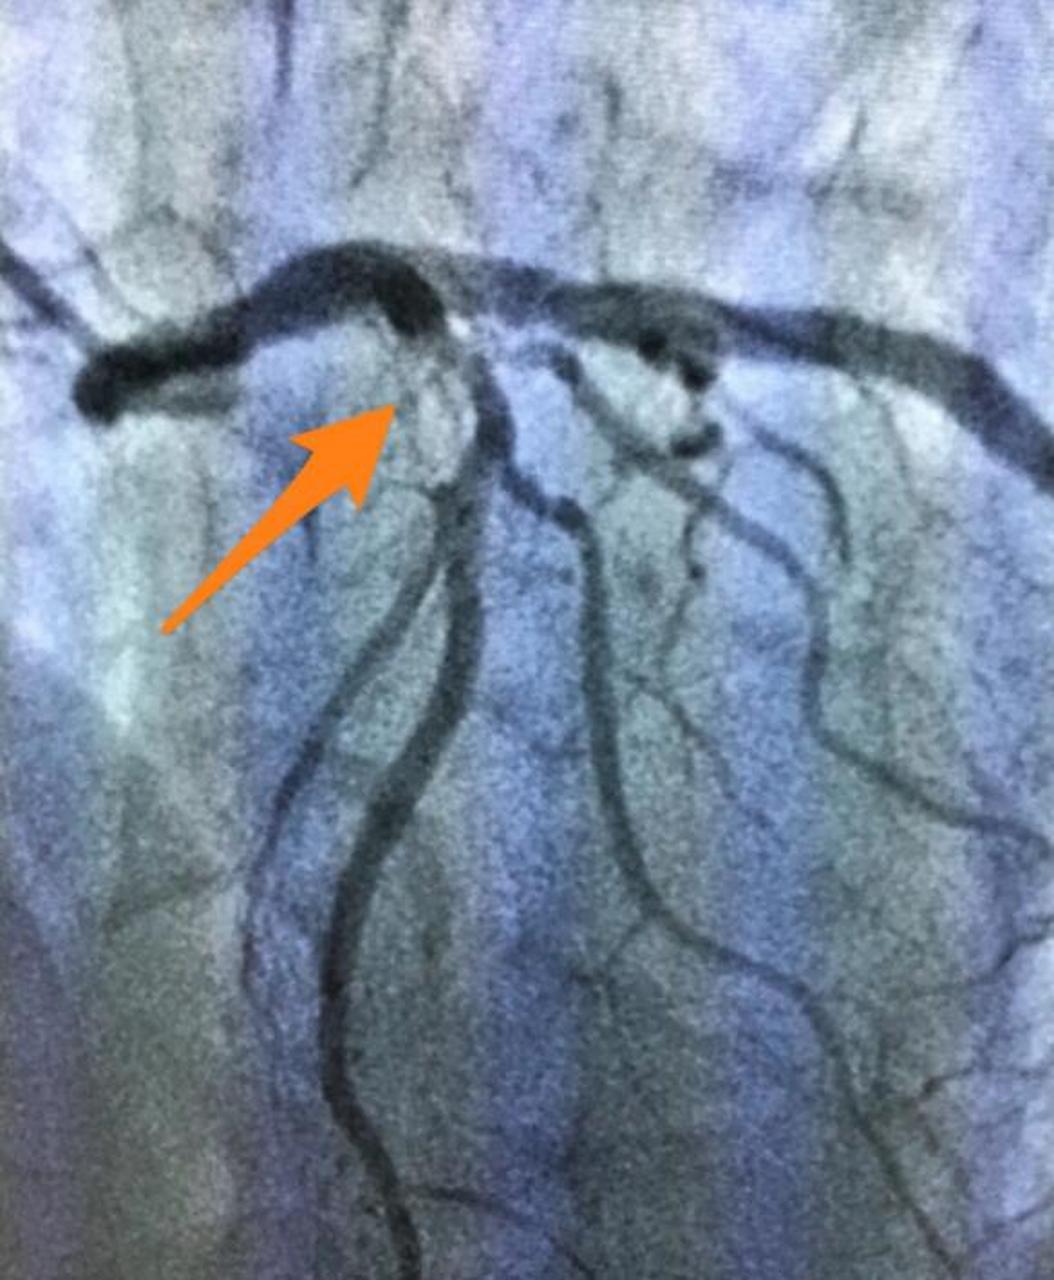

冠脉复杂病变(左前降支分叉病变,bskt治疗)#专业的事交给 - 抖音

于前降支进行药物球囊扩张后血流恢复timi3级,血管内超声(ivus)提示